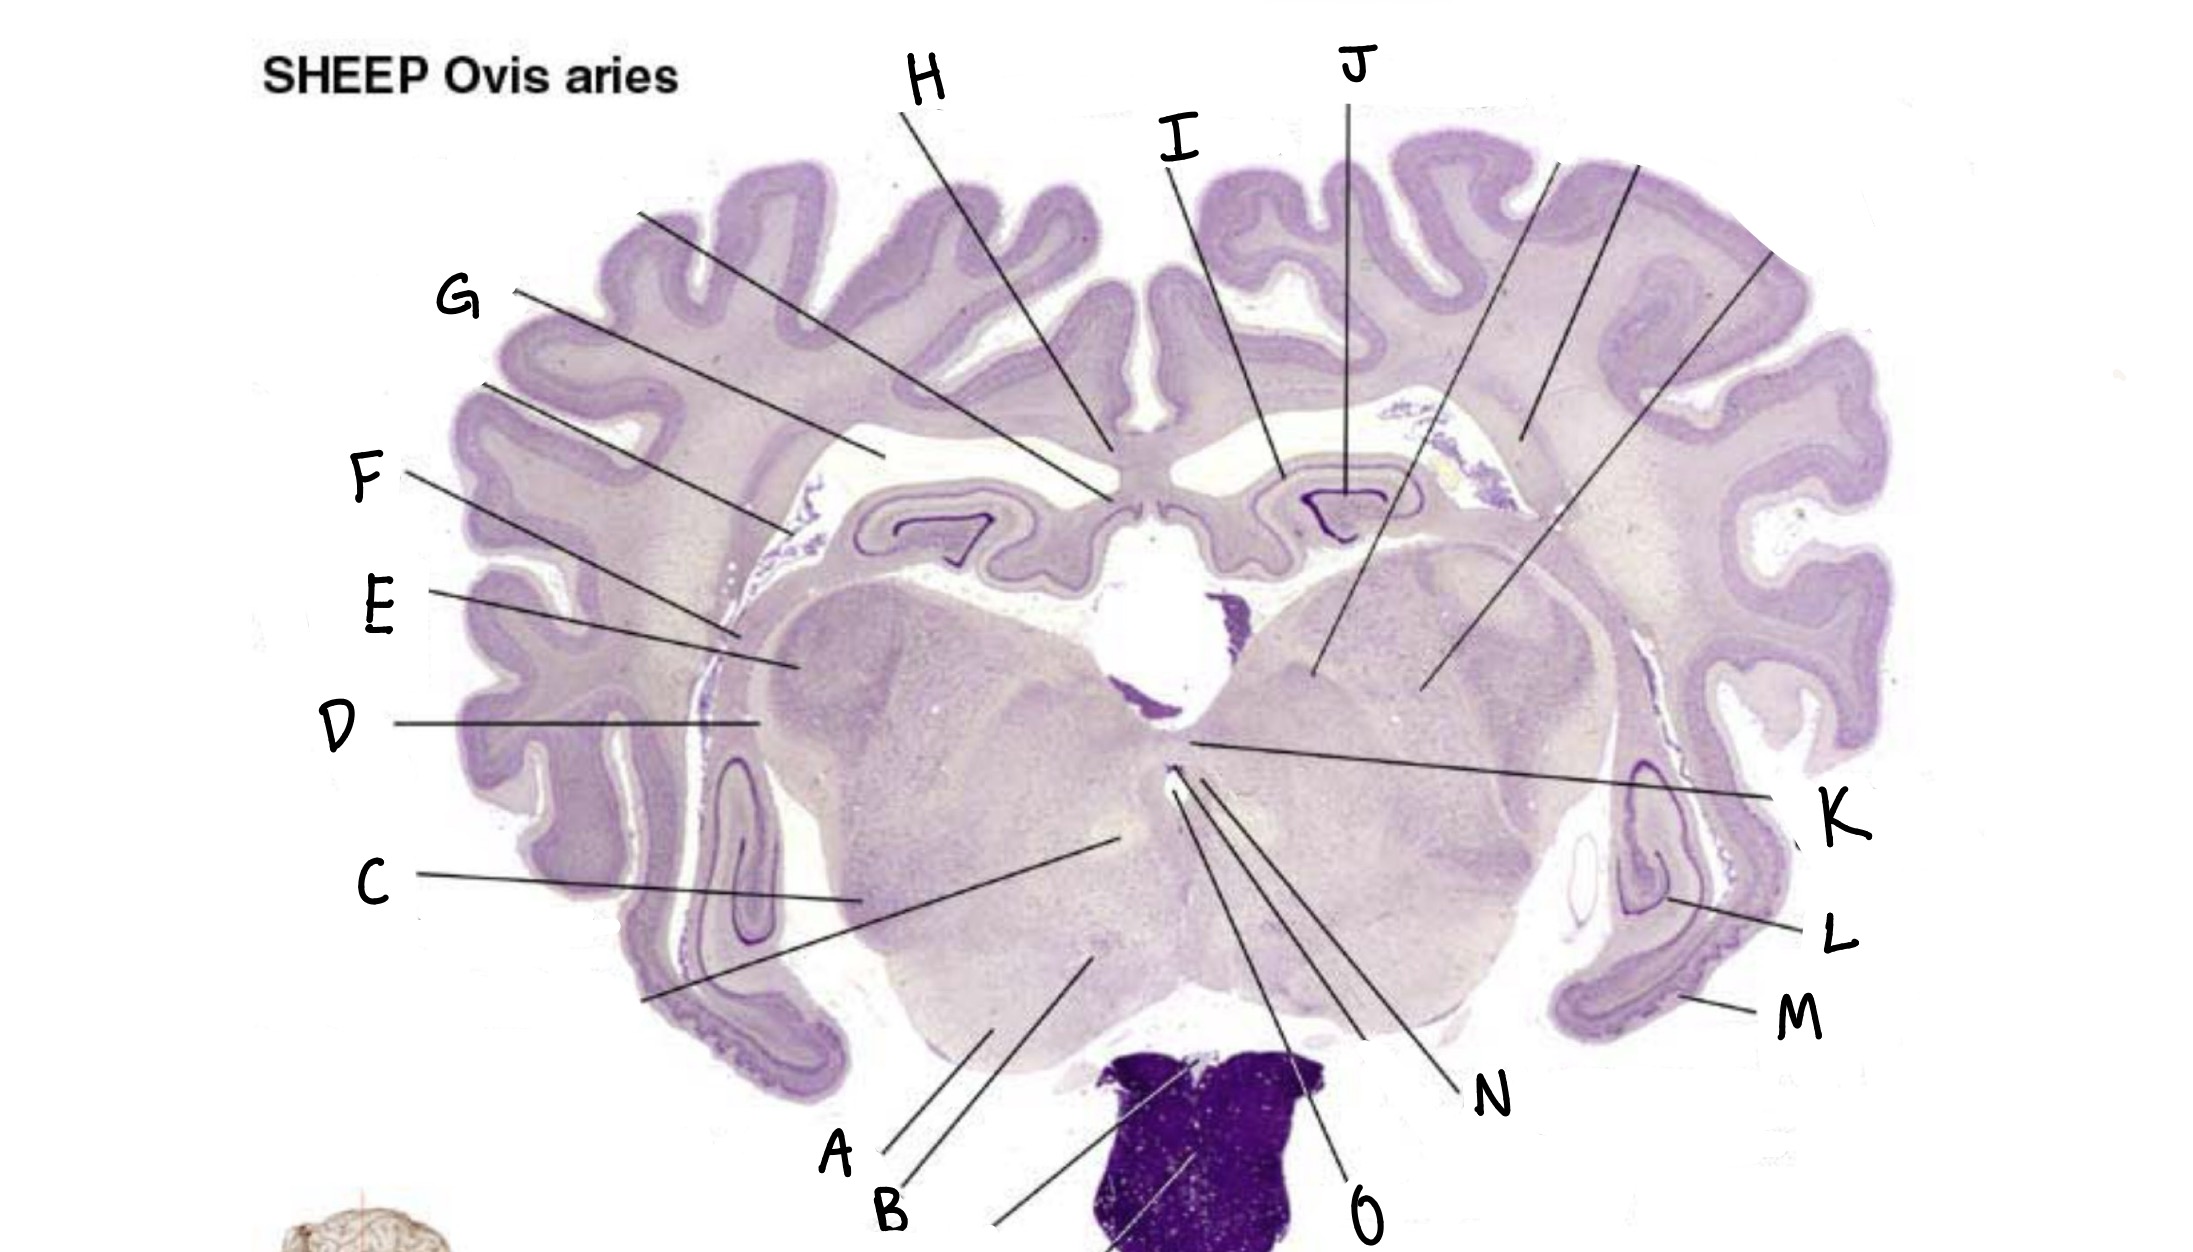

what is a

globus pallidus

caudate

what is b

pineal gland

what is c

dentate gyrus

what is d

cerebral aqueduct

what is e

entorhinal cortex

what is f

lateral geniculate nucleus

what is g

medial geniculate nucleus

what is h

periaqueductal grey

what is i

cerebral peduncle

what is j

optic tract

what is k

posterior commissure